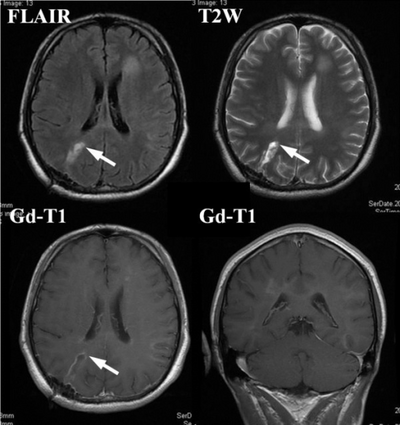

MRI diagnosis is based on lesions that are disseminated in time and space, meaning that there are multiple episodes and consisting of more than one area.[39] There are two kinds of MRI used in the diagnosis of tumefactive MS, T1-weighted imaging and T2-weighted imaging. Using T1-weighted imaging, the lesions are displayed with low signal intensity, meaning that the lesions appear darker than the rest of the brain. Using T2-weighted imaging, the lesions appear with high signal intensity, meaning that the lesions appear white and brighter than the rest of the brain. When T1-weighted imaging is contrast-enhanced through the addition of gadolinium, the open ring enhancement can be viewed as a white ring around the lesion.[40] A more specific MRI, Fluid attenuation inversion recovery (FLAIR) MRI show the signal intensity of the brain. Subjects with tumefactive multiple sclerosis may see a reduction of diffusion of the white matter in the affected area of the brain.[11]

High-intensity areas shrink after 1 month of steroid management ( Gd-enhanced lesions completely disappear), arrow(s) indicate biopsy points